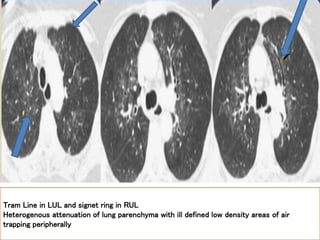

Tram Line in LUL and signet ring in RUL

Heterogenous attenuation of lung parenchyma with ill defined low density areas of air

trapping peripherally

Air trapping

Bronchial wall

thickening

with mucus

plugging

Tram Line inLUL and signet ring in RUL Heterogenous attenuation of lung parenchyma with ill defined low density areas of air trapping peripherally